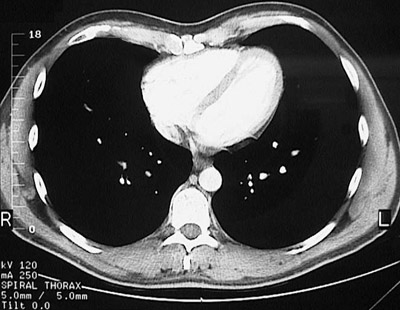

[T9] This is a normal chest CT scan demonstrating the right lung and left lung and pectoralis major muscle and right ventricle and interventricular septum and left ventricle and xyphoid process and descending aorta and azygous vein and esophagus and serratus anterior muscle and latissimus dorsi muscle and trapezius muscle and sacrospinalis muscle and transversospinal muscle in the upper chest.